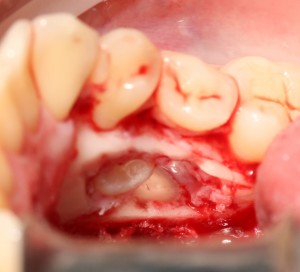

Костная «дверца» на время отделяется и убирается в физраствор, а мы видим следующее:

Это фолликулы и, частично, коронковые части сверхкомплектных зубов.

Теперь аккуратно нам нужно выделить сами зубы:

А вот они! Далее мы руководствуемся главным правилом хирурга-стоматолога: